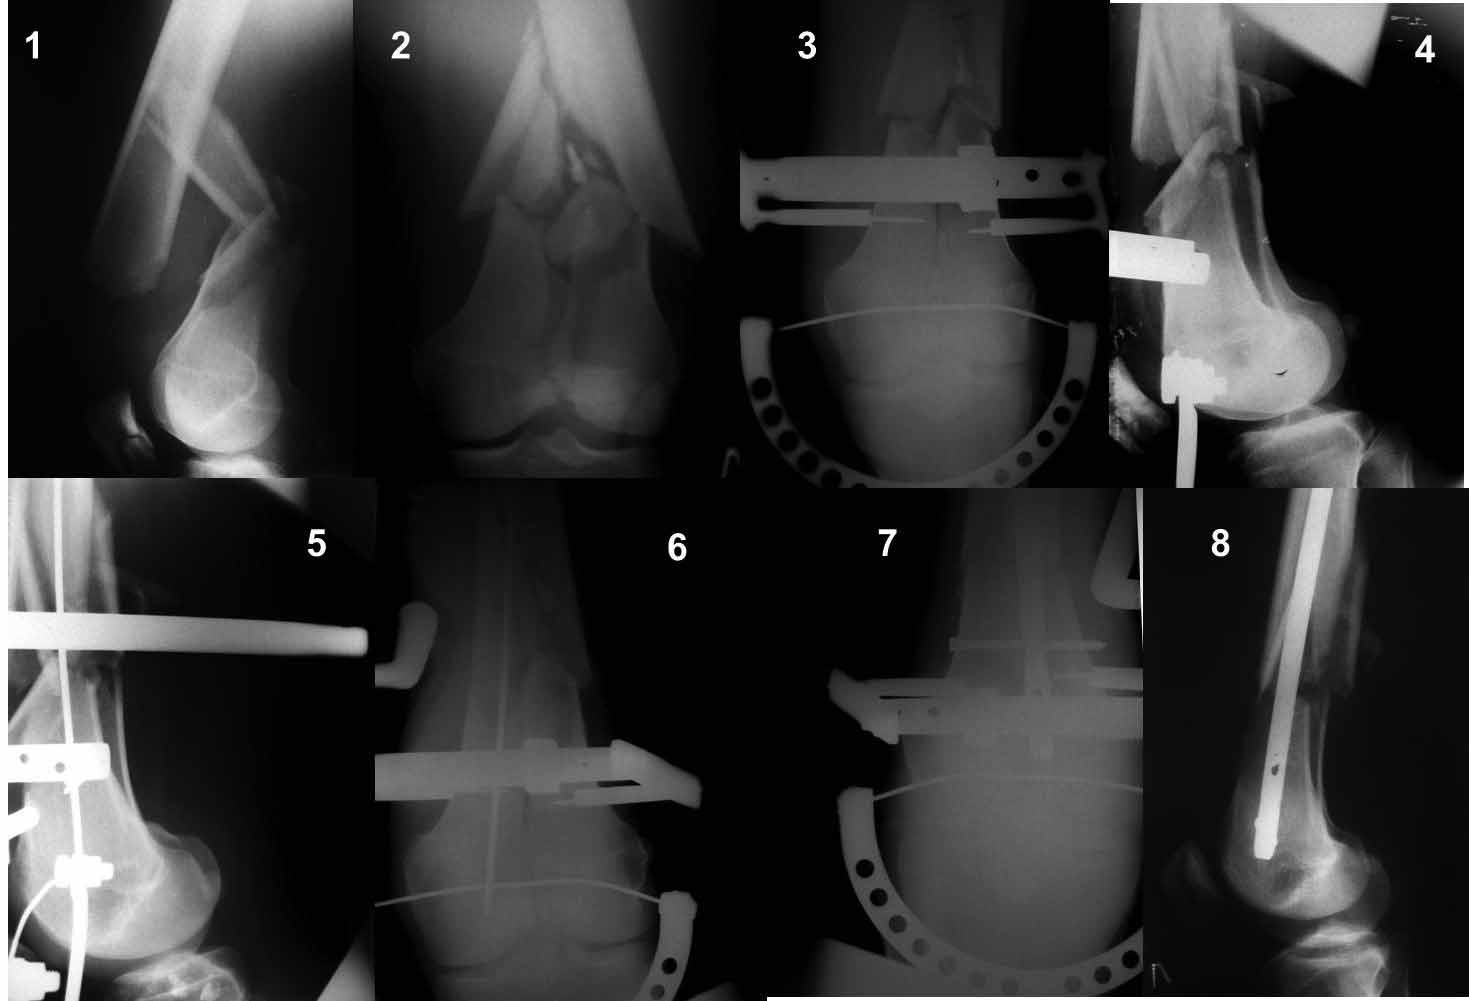

Re: перелом бедра

VlaD 21 Октябрь 2011, 02:08

Ну зачем же так. Всё-таки считается "золотым стандартом". Во вложенном файле коллаж из сохранившихся фотографий одной из операций. Всё сделано закрыто и без ЭОПа.